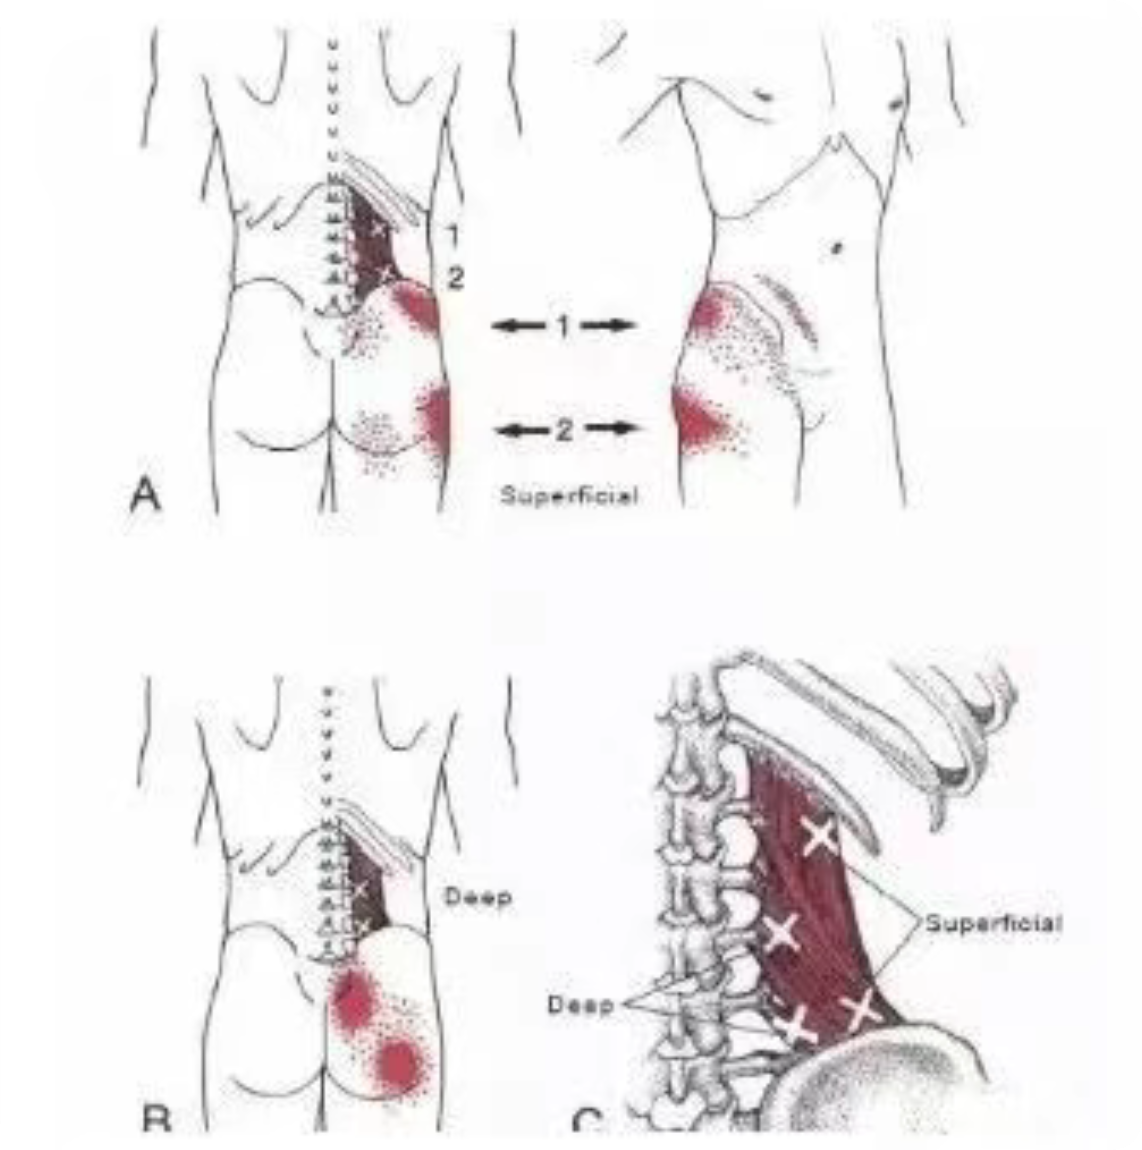

臀上皮神经是由腰1--3脊神经后外侧支组成。第2腰神经的后支紧贴第3腰椎横突顶端尖部向外侧走行,穿过深筋膜从骶棘肌外缘在深浅筋膜之间向下走行,在腰三角处穿过腰背浅筋膜,越过髂嵴分布于臀上部皮下,还有部分纤维入臀中肌和大腿后侧皮下。

股外侧皮神经:第三腰椎横突末端附近有腰丛神经中的股外侧皮神经通过,因此本综合征的疼痛可影响到大腿前外侧。

第三腰椎横突端后方紧贴着第二腰神经根的后支,当前屈及向对侧弯腰时,该后支被横突挑起或受磨损而引起该神经支支配区痛、麻,也能牵涉到第二腰神经前支而引起反射痛,达臀部及大腿前侧。第三腰椎横突前方深面有腰丛神经的股外侧皮神经干通过,并分布到大腿外侧及膝部。如横突过长、过大或伴有纤维织炎时,能使该神经受累并出现股外侧皮神经痛。此病变波及附近的闭孔神经甚至于肌神经时,疼痛也可出现于髋部或大腿。

2、症状轻者表现为一侧或两侧腰部酸胀、疼痛、乏力,休息后缓解,劳累及受凉、潮湿时症状加重;症状重者呈持续性疼痛,可向臀部、大腿后侧和内侧,个别病人可放射至小腿,腰部前屈和向健侧屈时症状加重。

3、患侧腰三横突尖部有明显的压痛,疼痛向臀部及大腿后侧放射,一般不过膝关节。有时患侧臀上皮神经也有压痛。压痛点用1%或0.5%普鲁卡因10~20mL注射后,疼痛及压痛消失。